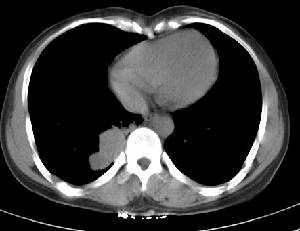

下叶后基底段近膈面见一椭圆形密度均匀增高的阴影,边界较清,其长轴指向内后方,考虑肺隔离症,建议增强扫描了解与主a联系!

右下肺隔离症可能性大,不除外炎性假瘤、神经原性肿瘤

1炎性假瘤,2神经原肿瘤待除外.

1.后纵隔神经原肿瘤,2.炎性假瘤。建议密切结合临床或抗炎治疗后复查。